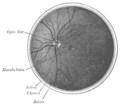

الجزء الداخلي من النصف الخلفي من مقلة العين اليسرى